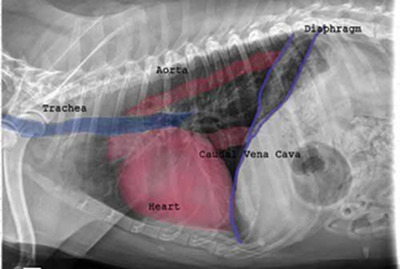

Radiography (x-ray) is used to determine if the heart is enlarged

(particularly the left atrium and left ventricle), if the veins from the

lungs to the heart are distended, or if fluid is beginning to develop in the

lungs.* X-rays also will show any enlargement of

the pulmonary vein, a classic symptom of congestive heart failure (CHF).

The VHS is not intended to diagnose CHF. It's purpose is to enable veterinarians to more accurately determine enlargement of the heart (called cardiomegaly or dilation) and the progression at which the enlargement is occurring, which usually is due to MVD. However, since MVD normally initially causes only the left atrium (LA) to enlarge, the VHS method is not precise enough to measure only the size of the LA. See for example, the x-ray at left, which shows that the VHS measurements entirely miss the bulbous enlarged LA in the upper right corner of the heart. (Image from Hezzell, 2018.)